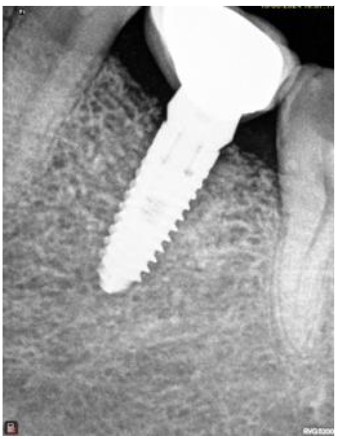

After a period of 5-month showing intraorally and radiographically the site from where bone core using trephine was taken for histological analysis; the same site where implant, Mis implant 3.75/11.5 was placed.

All sites healed uneventfully. There was no sign of post-operative infection. None of the patients showed any complications post-surgical. Additionally, none of the surgical sites needed additional hard or soft tissue grafting. Upon implant placement, the surgical sites showed appropriate healing as it is seen in any other grafted areas. Furthermore, there was adequate bucco-lingual width of the grafted for Implants placement. Implants placed showed satisfactory primary stability.